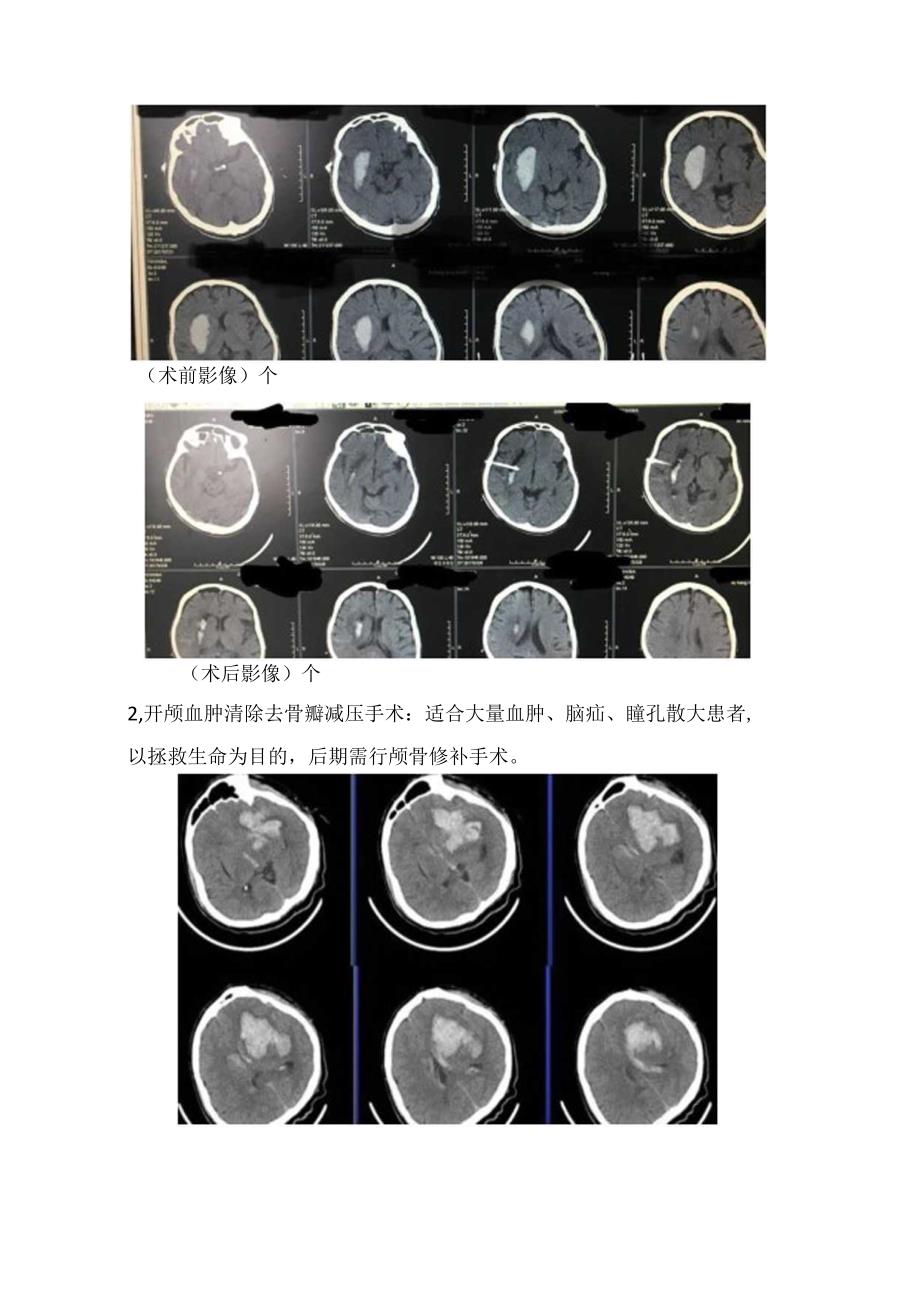

3、脑屏障破坏、毒素对周围组织刺激;脑缺血。3、颅内压增高:脑疝-死亡需要外科处理患者1、大脑半球出血30m1.者;2、小脑出血1Om1.或血肿直径3cm、伴有脑干压迫和脑积水的患者。目前主张早期进行手术,如果在继发性脑损害前尽快清除血肿,那么神经功能可获得较好恢且,减轻后遗症。外科手术方式1、钻孔引流:适合脑室出血或者病情不严重的脑实质内出血患者,创伤小,一般需要待6小时后血肿稳定后操作,有再出血的风险。(术前影像)个(术后影像)个2,开颅血肿清除去骨瓣减压手术:适合大量血肿、脑疝、瞳孔散大患者,以拯救生命为目的,后期需行颅骨修补手术。(术前影像)个(术后影像)t3、小骨瓣开颅手术:适合血肿较大,有意识障碍但尚未脑疝的患者,创伤小、显微镜卜止血彻底,术后骨瓣复位,避免后期做颅骨修补手术。(术前影像)t(术后影像)t4、神经内镜下微创手术:脑功能哑区入路,减少传导束损伤,直视下快速清除血肿减压,可控制深部出血,骨窗更小,透明鞘内操作,对周围脑组织损伤更小。(手术示意图)t(术前影像)t(术后影像)t